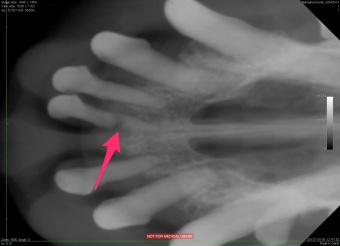

この写真の矢印のところ・・・分かりますよね?歯が折れています。でもこれは歯肉のなかで外からは見えない部分の事なので、こんな事が起きているなんて、レントゲン撮影なしではわかりません。でも歯が折れていることで痛みを感じています。